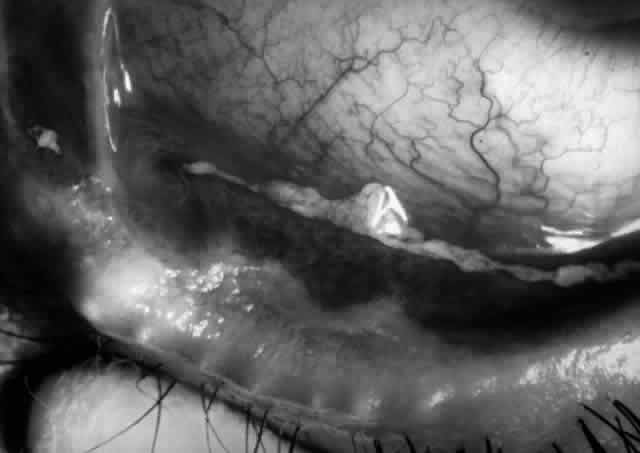

Clinically, the ocular disease in cicatricial pemphigoid (OCP) may present unilaterally in the form of a chronic, recurrent catarrhal conjunctivitis, but it eventually becomes bilateral. Subepithelial fibrosis is characteristic of stage 1 of OCP (Fig. 7). Stage 2 shows fornix foreshortening (Fig. 8), and symblepharon formation is the hallmark of stage 3 (Fig. 9). Stage 4, end-stage disease, is characterized by ankyloblepharon and surface keratinization (Fig. 10). Obstruction of the lacrimal ductules and meibomian gland ducts eventually produces an unstable tear film and progressive sicca syndrome, but it is to be emphasized that OCP is not a dry-eye syndrome until late in the disease course.20 Trichiasis and entropion occur because of the subepithelial fibrosis, with eventual keratopathy, corneal neovascularization, and corneal ulceration and scarring.20

Fig. 8. Stage 2 cicatricial pemphigoid, with fornix foreshortening and subepithelial fibrosis without frank symblepharon formation.